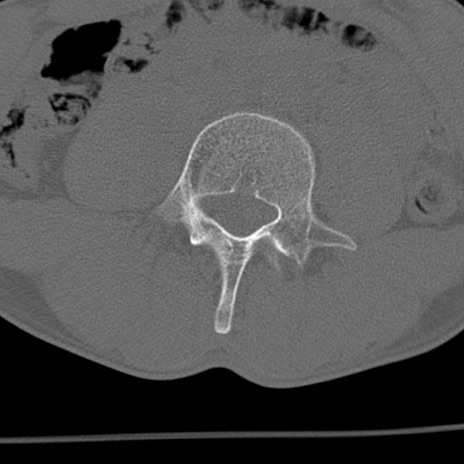

症例3 腰椎CT(横断像)

腰椎CT